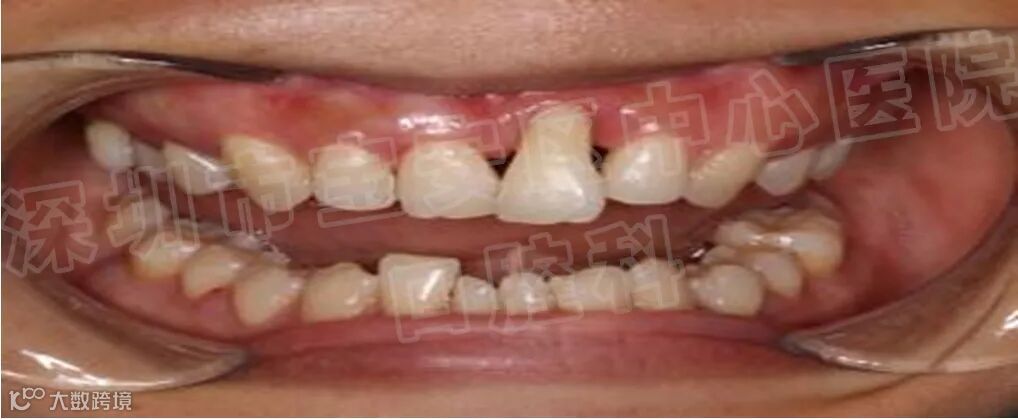

牙周病 是牙齿支持组织,包括牙龈、牙骨质、牙周韧带和牙槽骨因炎症所致的一种疾病,是最常见的口腔疾病之一,也是导致牙齿丧失的一个主要原因。但患者并非所有这些组织都同时患病,视局部炎症的轻重及范围,牙周病可分为龈炎和牙周炎二大类。

在咬合时,若咬合力过大或方向异常,超越了牙周组织所能承受的咬合力量,致使牙周组织发生损伤的咬合,称为创伤性咬合。创伤性咬合包括咬合时的早接触、干扰、夜间磨牙等。

经过上述治疗之后,大多数患者的牙周炎症可以得到消除,松动的牙齿慢慢稳固,患者的咀嚼功能明显提高。但是,经过牙周基础治疗之后,部分患者仍然会有个别牙齿,甚至多颗乃至整个牙弓中的余留牙齿松动,难以行使正常的咀嚼功能,一旦出现上述问题,则需要采用牙周炎手术治疗。牙周翻瓣,牙周再生,骨再生等手术去恢复牙龈炎症,牙槽骨吸收等问题